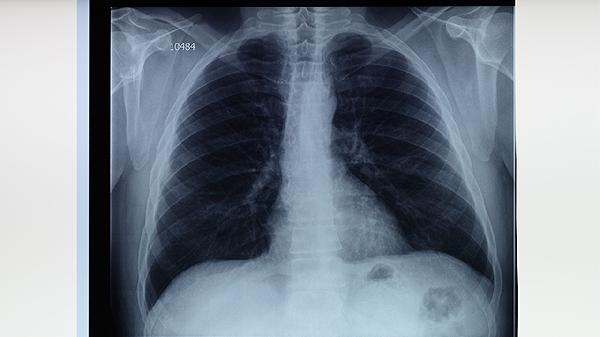

肺結(jié)核對患者的危害主要包括肺部組織損傷、全身消耗癥狀、傳染風(fēng)險、并發(fā)癥及心理影響。肺結(jié)核是由結(jié)核分枝桿菌引起的慢性傳染病,主要危害有肺部功能損害、營養(yǎng)不良、傳染性威脅、多系統(tǒng)并發(fā)癥、心理健康問題。

肺結(jié)核病灶可導(dǎo)致肺組織壞死、空洞形成,嚴重時引起肺纖維化或毀損肺,表現(xiàn)為持續(xù)性咳嗽、咯血、呼吸困難。長期未治療可能發(fā)展為慢性肺源性心臟病。需通過胸部CT評估病變范圍,治療需規(guī)范使用異煙肼片、利福平膠囊、吡嗪酰胺片等抗結(jié)核藥物。

肺結(jié)核患者應(yīng)堅持6-9個月規(guī)范用藥,定期復(fù)查肝腎功能和胸部影像。注意保持居室通風(fēng),咳嗽時掩住口鼻,痰液需消毒處理。飲食需保證每日優(yōu)質(zhì)蛋白攝入,如雞蛋、魚肉、豆制品,配合適量有氧運動增強體質(zhì)。家屬應(yīng)協(xié)助監(jiān)督服藥,觀察藥物不良反應(yīng),出現(xiàn)視力模糊、關(guān)節(jié)痛等癥狀時及時就醫(yī)。治愈后仍需每年進行胸部X線隨訪,警惕復(fù)發(fā)可能。